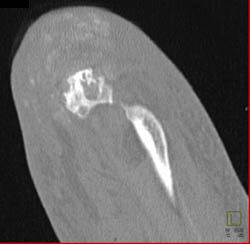

Gout